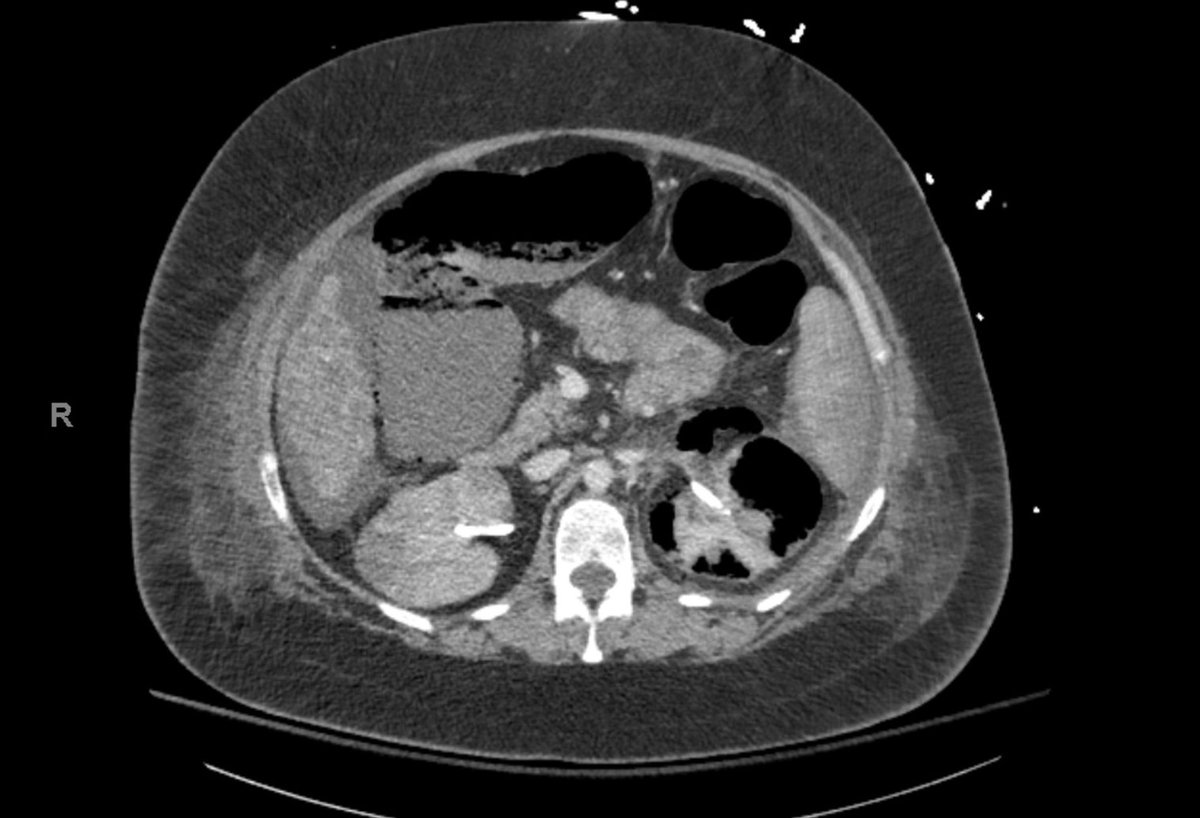

A case of malignant melanoma metastatic to the bladder. Presented with severe anemia secondary to intermittent gross hematuria. Perhaps not as rare as a glance at the literature may suggest! @FoleyAndFollies tinyurl.com/5mjumnrb